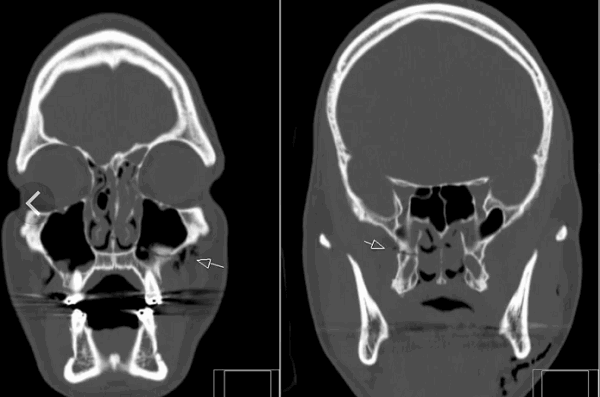

(Слева) Рентгенограмма в прямой проекции: левосторонний перелом крестца во II зоне, вызванный боковой компрессией. Обратите внимание на угловую деформацию дугообразных линий слева и сравните их с нормальными плавными дугообразными линиями справа.

(Справа) КТ, аксиальный-срез: тяжелый оскольчатый перелом крестца, полученный в результате аварии при занятии парасейлингом. Перелом включает поперечный компонент и двусторонние вертикальные переломы, проходящие через крестцовые отверстия, а также вертикальный перелом, проникающий в крестцовый канал. (Слева) Рентгенограмма в прямой проекции: перелом крестца во II зоне. Переломы в этой области легко не заметить из-за экранирования их мягкими тканями. Наиболее значимый признак в данном случае-это нарушение непрерывности латерального контура крестца. Сравните его с нормальным противоположным контуром крестца.

(Справа) Накосом фронтальном КТ-срезе (соответствующем плоскости крестца) этого же пациента перелом определяется более четкой. (Слева) На аксиальном КТ-срезе у ребенка определяется перелом правой боковой массы крестца типа «зеленой веточки». Слева виден нормальный апофиз, отличающийся округлыми склерозированными краями.